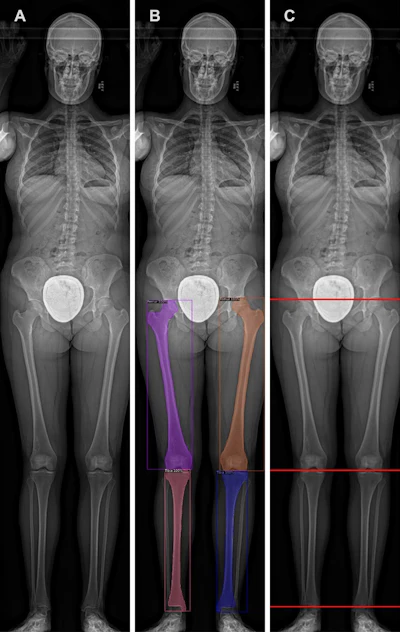

В этом исследовании авторы стремились использовать искусственный интеллект для улучшения этих методов путем обучения модели сверточной нейронной сети (CNN) для автоматического измерения длины бедренно-большеберцовой кости на рентгеновских изображениях у педиатрических пациентов, различающихся по расовому признаку.

Модель CNN была обучена сегментировать бедренную кость и большеберцовую кость на рентгеновских снимках и измерять общую длину голени, бедренной кости и большеберцовой кости. Результаты показали, что средняя абсолютная ошибка измерений модели составила 0,25 см для бедренной кости, 0,27 см для большеберцовой кости и 0,27 см для большеберцовой кости. 0,33 см для составных нижних конечностей.

Затем измерения искусственного интеллекта были использованы для создания кривых роста бедренной и большеберцовой костей, и исследователи сравнили их с кривыми, полученными по методу Андерсона-Грина.